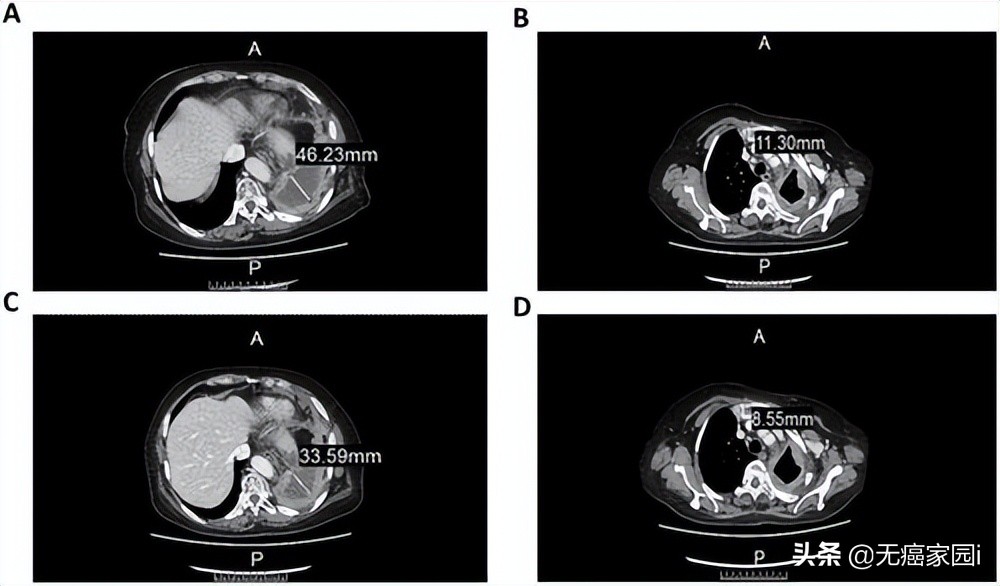

经3周期的治疗后,CT图像显示细胞疗法在治疗肿瘤方面具有一定的疗效。具体来说,左肺包裹的胸腔内液体从46.22mm减少到 33.59mm(图 2A ~2C),而前气管-后腔静脉间质区域的淋巴结从11.3mm减少到8.55mm(图2B~2D)。